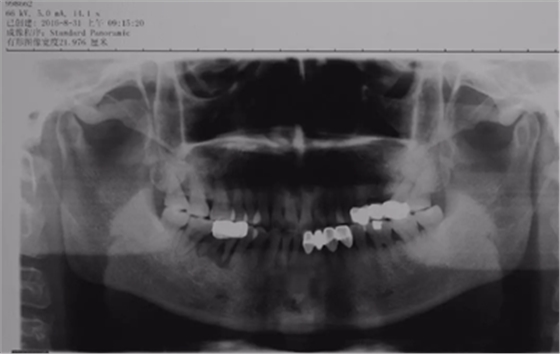

3、术前全景片

46牙烤瓷冠修复,根折伴大范围骨吸收。(摄于2016年8月31日)